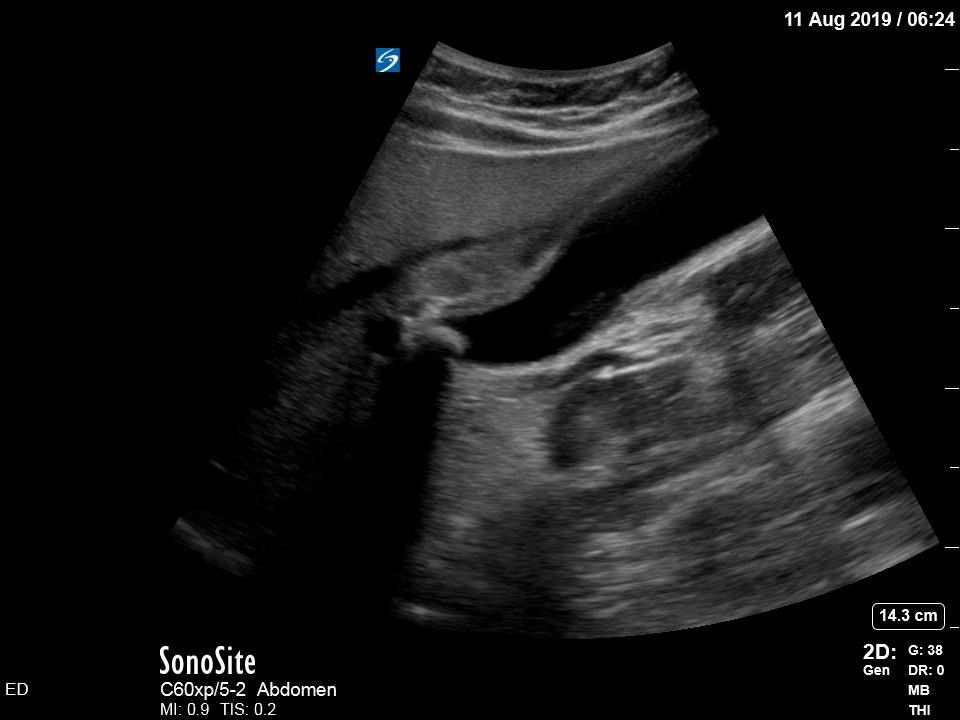

The treating house officer suspected an alternative pathology and bedside ultrasound was performed.

The appearance is typical of acute cholecystitis. The patient was started on IV antibiotics. Images were shown to the surgical registrar who accepted the patient for admission. Formal ultrasound confirmed the findings and the patient went for laparoscopic cholecystectomy within 24hrs. At operation, there was a grossly inflamed gallbladder with an 11mm stone in the neck.

Ultrasound is the formal imaging study of choice for diagnosing gallstones and acute cholecystitis, which makes it a particularly useful POCUS study. The four sonographic signs of acute cholecystitis are:

- Cholelithiasis (stones in the gallbladder, especially if non-mobile)

- Gallbadder wall thickening (there are various published criteria and rules of thumb but generally >4mm is considered abnormal – though it is more about the edematous/irregular appearance than the specific number)

- Pericholecystic fluid

- Sonographic Murphy sign (the patient is tender when the probe presses on the gallbladder)

Notice the typical appearance of the gallstone – the anterior face reflects ultrasound producing a hyperechoic (bright) surface. Because no sounds waves pass through the stone, the area behind it cannot be imaged and instead we see the artefact known as posterior acoustic shadow.